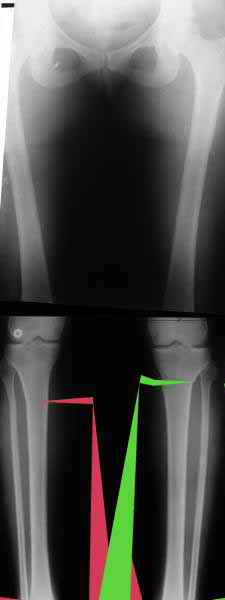

Картинки - в приложении.Будут вопросы - готов ответить.

Ещё картинка - схема. Хотя у Соломина всё написано.

Вот ещё картинки, которые отправлял в Ортопод. Коррекция кривизны и удлинение на 3 см.